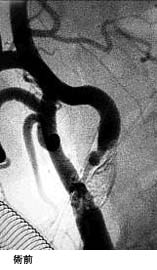

(3)頸動脈狭窄症に対するステント留置術

(現在、ステントは保険適応となっておりません。)